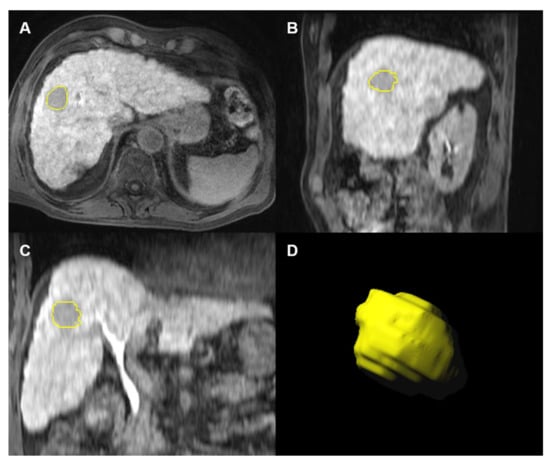

2.4. Segmentation and Radiomics Feature Extraction